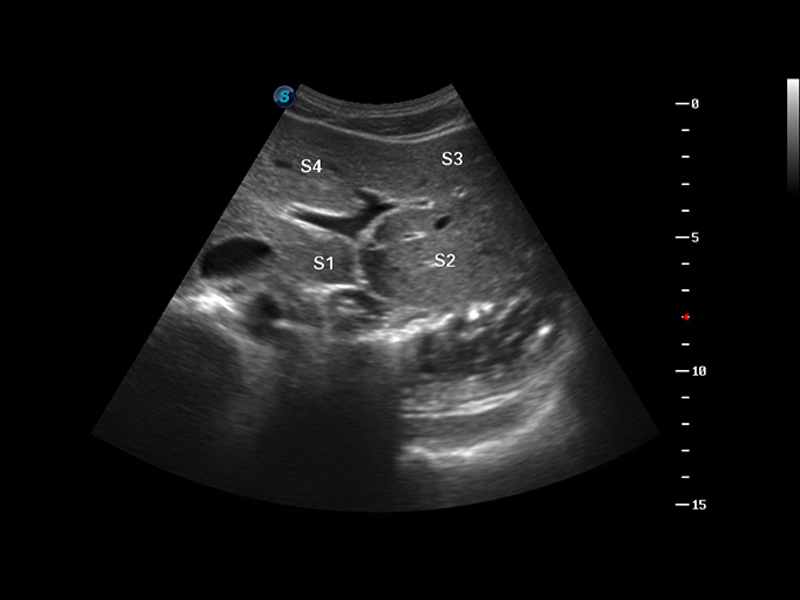

S8 EXP便携式彩色多普勒超声诊断仪是银河集团官网研发的高端全身应用型便携彩超。高通道的VIS平台融合可视化(Visual)、智能化(Intelligent)和人性化(Smart)的特点,配以银河集团官网自主研发生产的探头大家族,使您能够快速、准确的获得病人信息,提高工作效率的同时减轻疲劳。

成像技术

多波束形成器

μ-Scan微米成像

谐波成像

实时宽景成像

空间复合成像

3D/4D成像